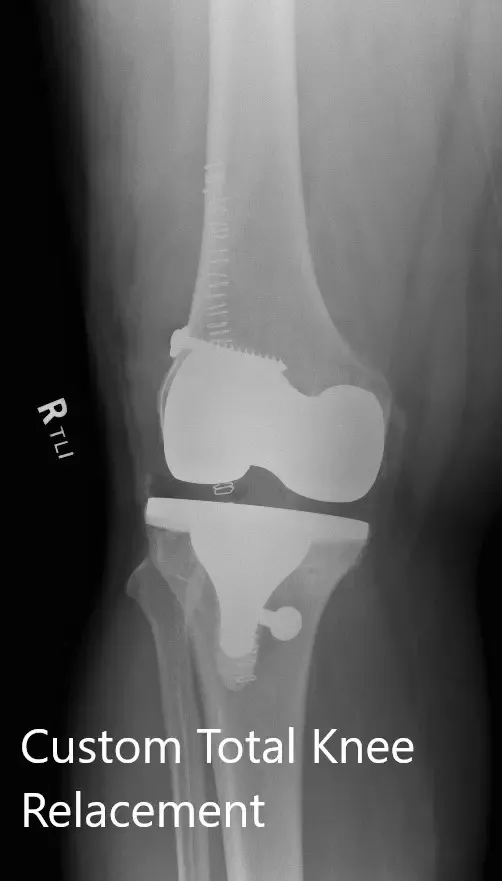

Imágenes postoperatorias que muestran vistas AP y laterales de la rodilla derecha